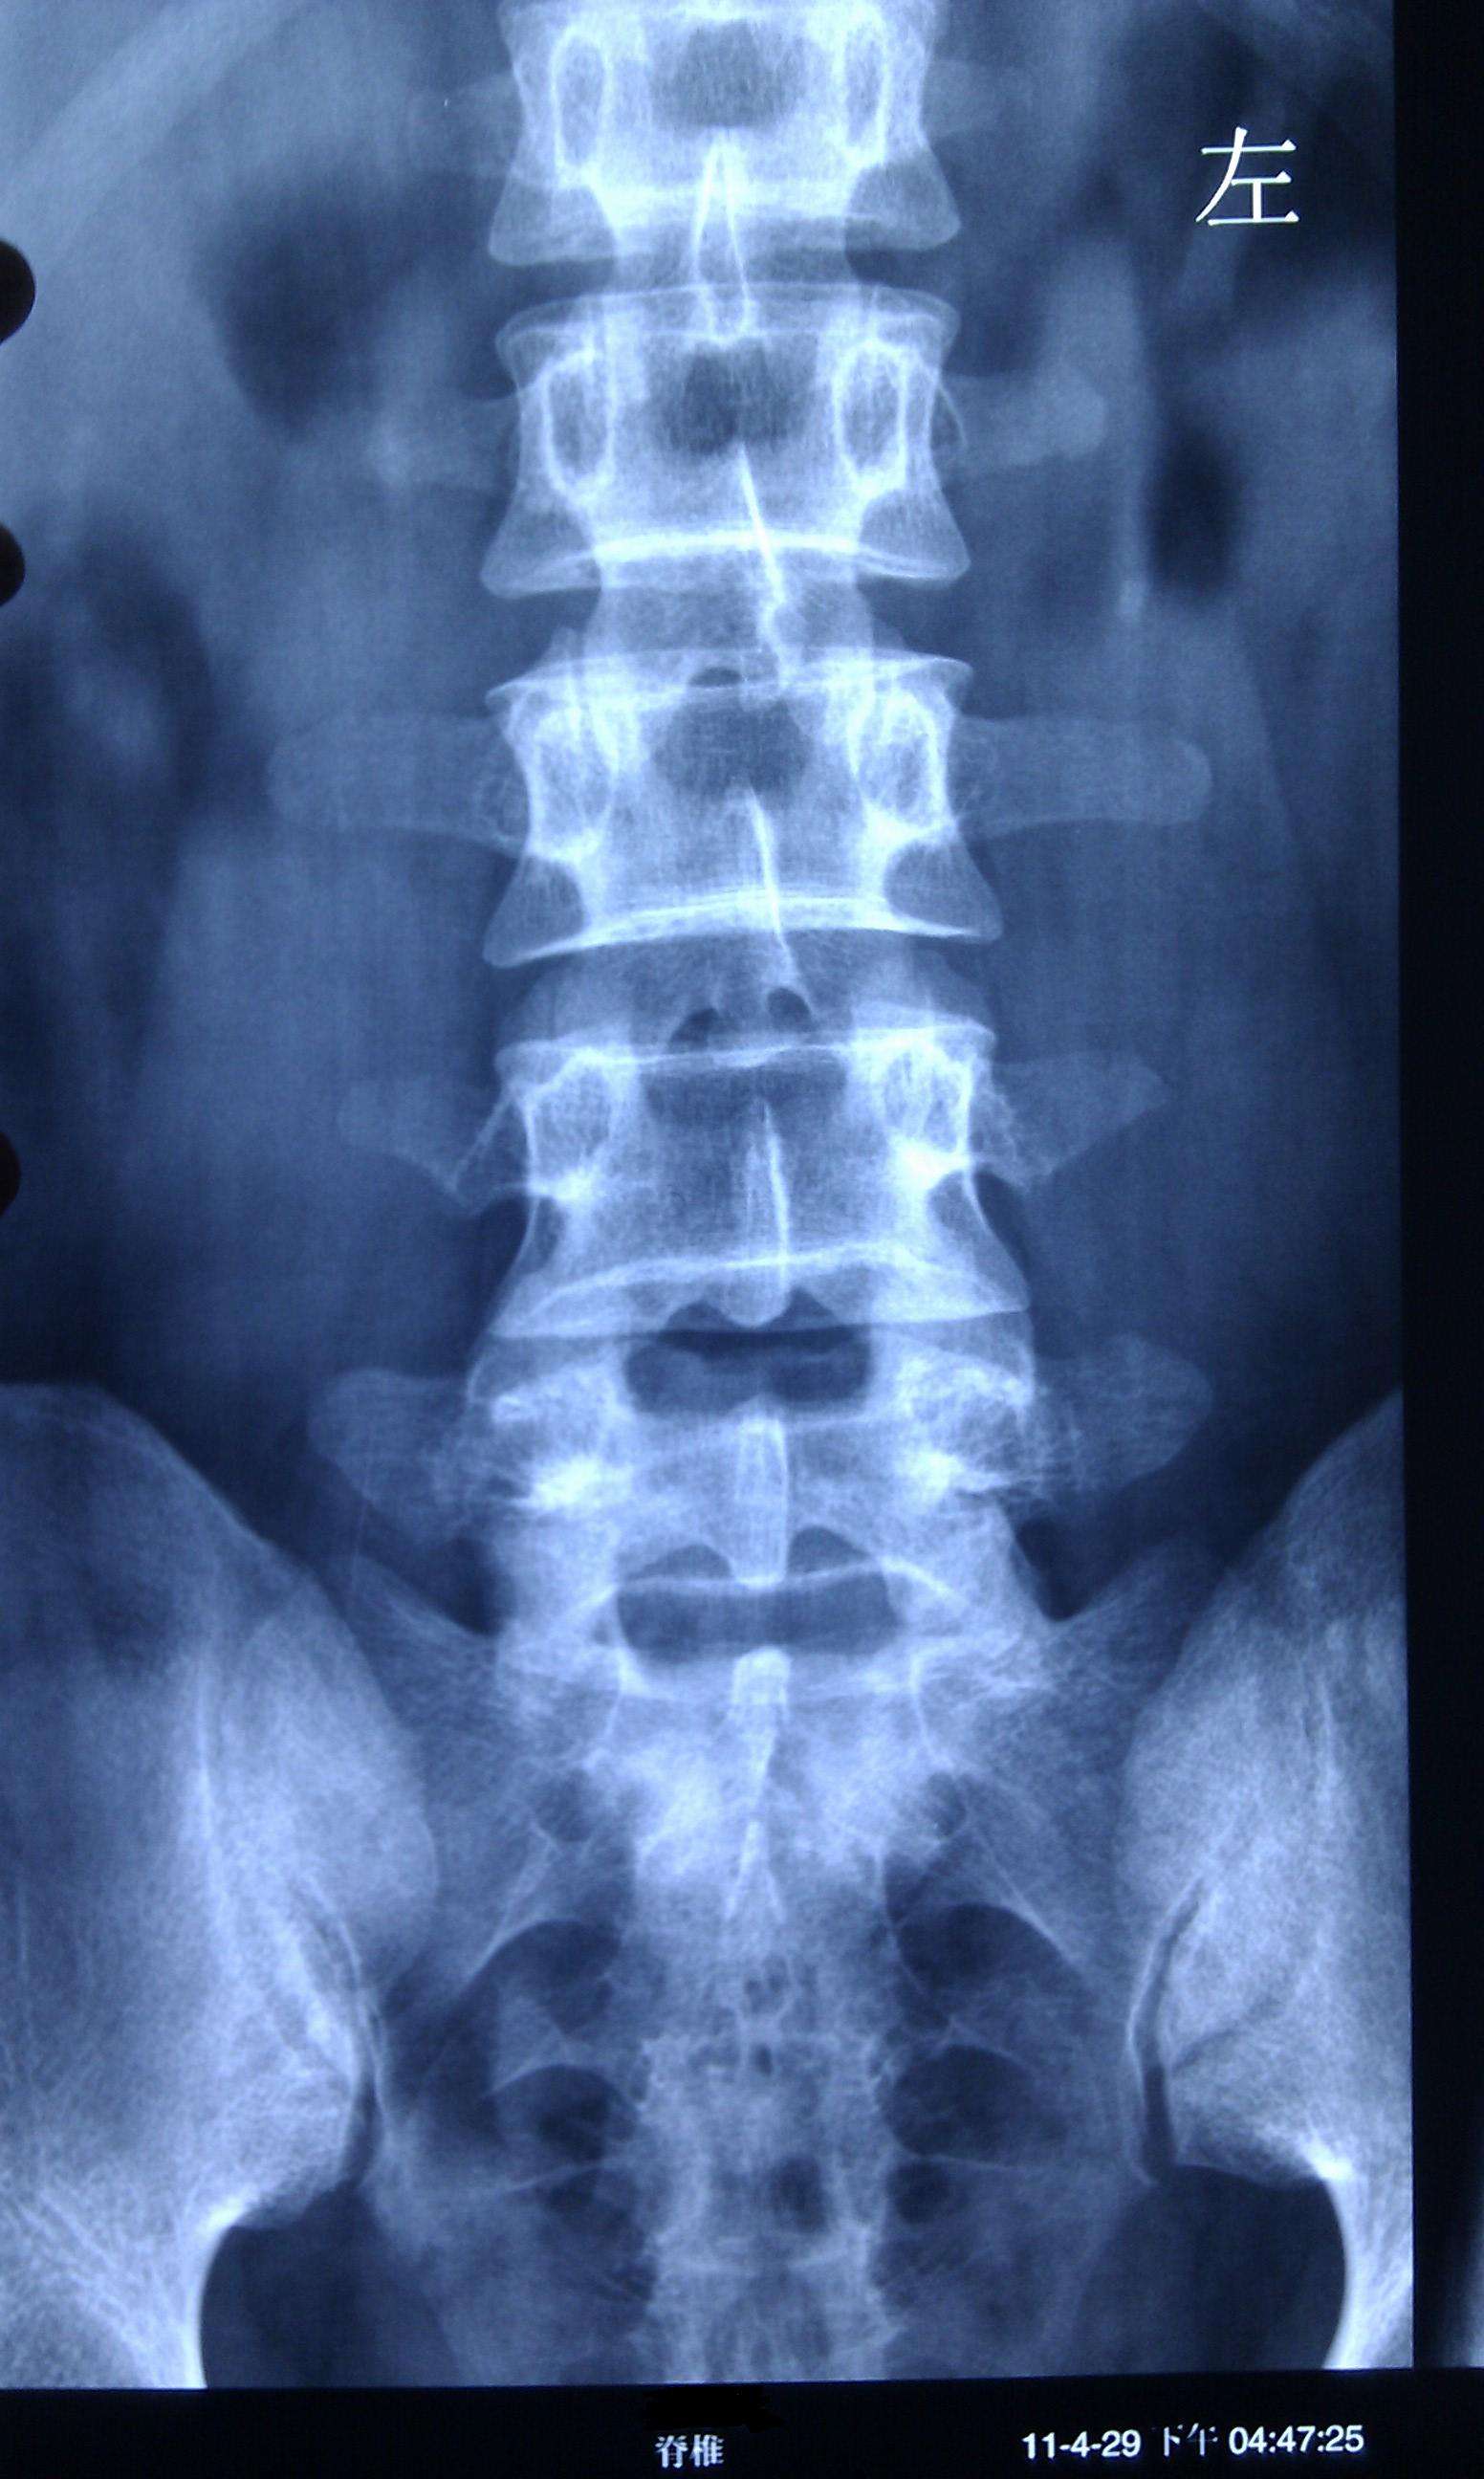

4.X线可示有第三腰椎横突过长或左右不对称。

临床上腰三横突综合征被误诊为腰椎间盘突出症的并不少见。腰三横突综合征在出现腰腿部疼痛、活动受限等方面时与腰突症状相似。但是,腰三横突综合征多为双侧第3腰椎横突部有明显压痛点,疼痛沿大腿向下反射至膝平面以上,弯腰及旋转时腰部疼痛加重,腰部活动受限尤以前屈、后伸明显。并且可在腰三横突顶端有固定压痛并可能触及到活动结节和条索状物,或有肌纤钙化后的剥离感,侧卧屈髋试验阳性,直腿抬高及加强试验阴性。腰椎X线片可显示第三腰椎横突肥大。一般瘦长体型的人多发。